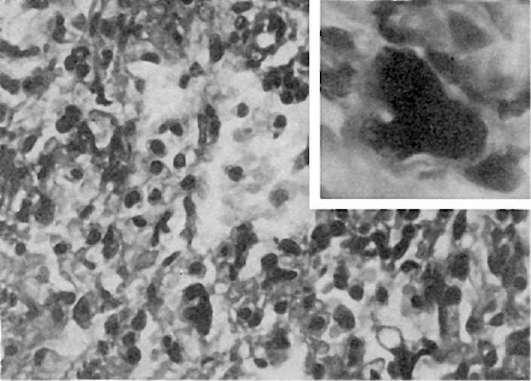

лимфогистиоцитарной инфильтрацией и выраженной десквамацией эпителиальных клеток. В цитоплазме десквамированных клеток находят фуксинофильные включения, увеличенные в размерах ядра содержат включения аденовируса. Такие аденовирусные клетки (рис. 252) являются маркером аденовирусной инфекции. У детей до 1 года нередко возникает пневмония, связанная со специфическим действием аденовируса -аденовирусная пневмония (см. рис. 252). В экссудате, который состоит из белковых масс с незначительным числом макрофагов, лимфоидных клеток, нейтрофилов и альвеолярного эпителия, обнаруживаются аденовирусные клетки. В межальвеолярных перегородках среди пролиферирующих септальных клеток также встречаются аденовирусные клетки. Иногда в альвеолах образуются гиалиновые мембраны.

Рис.

252. Аденовирусная инфекция. Вверху справа - аденовирусная клетка